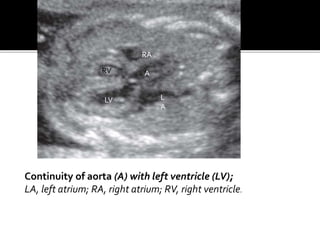

Continuity of aorta (A) with left ventricle (LV);

LA, left atrium; RA, right atrium; RV, right ventricle.

Continuity of aorta(A) with left ventricle (LV); LA, left atrium; RA, right atrium; RV, right ventricle. L A RA A LV RV